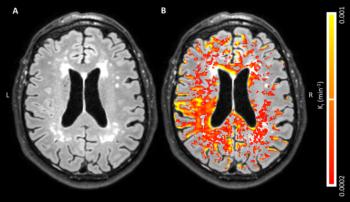

Figure 2. A, Axial fluid-attenuated inversion recovery image in an 80-year-old woman healthy control sub¬ject with, B, corresponding blood-brain barrier leakage rate (Ki) maps superimposed. Voxels with low signal-to-noise ratio in MRI signal intensity were removed, and leakage rate map was masked to cerebrum.